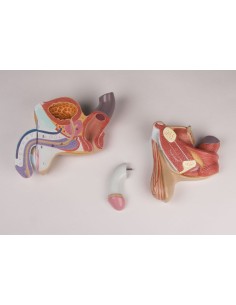

Pelvis masculin 3B Scientifique avec ligaments, vaisseaux, nerfs, plancher pelvien et...

Modèle anatomique du squelette du bassin d'un homme 3B Scientific H21/1